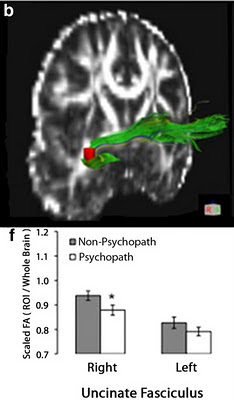

In the DTI study of structural connectivity, 13 non-psychopaths were compared to 14 psychopaths, 7 of whom were low-anxious or primary psychopaths and 7 were high-anxious/secondary psychopaths.

3 The

uncinate fasciculus (UF) is the main pathway connecting the vmPFC and the anterior temporal lobe (including the amygdala). Fractional anisotropy (FA), a measure of white matter structural integrity, was compared between the groups for regions of interest (after scaling for overall whole brain FA, which was reduced in the psychopaths). For comparison, FA in other frontal-temporal tracts was examined. Results indicated that FA was indeed reduced in the right UF, which replicates an earlier study (

Craig et al., 2009).

Fig. 1 (modified from Motzkin et al., 2011). DTI results: reduced white matter integrity is specific to the right UF in psychopaths. b, The UF ROI (red) superimposed on an entire UF tract, as computed with tractography. f, Bar plots of mean scaled FA values in the UF. Psychopaths exhibited significantly lower scaled FA values only in right UF. Error bars indicate SEM. *p < 0.05. Resting state fMRI, which measures spontaneous, low-frequency fluctuations in